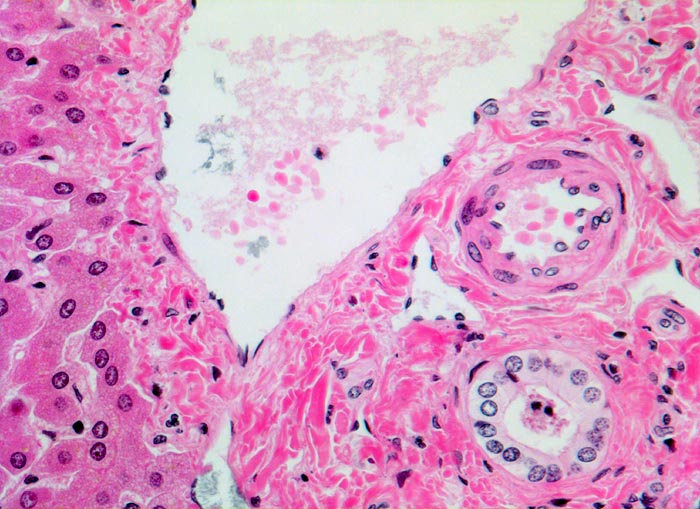

Meist findet sich eine grobtropfige oder gemischttropfige Verfettung des Parenchyms. Schon im Frühstadium der alkoholischen Steatohepatitis kann eine perizelluläre Maschendrahtfibrose, perisinusoidale und perivenuläre Fibrose mit Beginn in der Zone 3 festgestellt werden. Die Kombination von perivenulärer und perizellulärer (> 1096) Fibrose wird bei starker Ausprägung mit Arealen von dichter Kollagenfaserbildung auch als zentrale sklerosierende hyaline Nekrose bezeichnet. Wenn der Vernarbungsprozess fortschreitet, kann die perivenuläre Fibrosezone mit vernarbten Portalfeldern verschmelzen. Zentralvenen verschwinden oder sind stark in der Anzahl reduziert. Eine Phlebosklerose oder Obliteration der Zentralvenen kann hinzukommen. Breite Bänder von fibrotischem Gewebe mit Ductulusproliferationen und gemischtem Entzündungsinfiltrat umgeben die bei alkohlischer Zirrhose meist kleinen Regeneratknoten (=mikronoduläre Leberzirrhose mit Regeneratknoten von weniger als 3mm Durchmesser). Bei längeren Abstinenzphasen kann sich aufgrund der gesteigerten Regeneration auch eine gemischtknotige Zirrhose ausbilden. Ein gleichzeitiges Vorliegen einer Steatose oder Steatohepatitis (Steatose+neutrophile Granulozyten) in einer alkoholischen Leberzirrhose signalisiert in der Regel einen fortgesetzten Aethylabusus. Typisch für alkoholtoxische Leberschädigung sind Mallory-Denk Körperchen (> 3021), Megamitochondrien (> 3022) und eine Zellschwellung (=Ballonierung) aufgrund einer gestörten Albuminausschleusung. Oft können mässige Mengen von Hämosiderinablagerungen vor allem in den Kupffer Zellen nachgewiesen werden. Weitgehend identische morphologische Veränderungen wie bei der aethylischen Leberschädigung finden sich auch bei der nicht alkoholischen Steatohepatitis (NASH) d.h. bei Patienten, die keinen oder nur wenig Alkohol konsumieren.

• Zerstörte Läppchenarchitektur mit diffusem feinknotigem Umbau des Leberparenchyms.

• Breite Fibrosebänder mit Ductulusproliferation und gemischter Entzündung.

• Perivenuläre Fibrose und perizelluläre Maschendrahtfibrose in Zone 3.

• Verminderte Anzahl Zentralvenen.

• Mallory-Denk Körperchen

• Megamitochondrien.

• Hydropische Zellschwellung.

• Überwiegend makrovesikuläre, teils gemischttropfige Verfettung der Leberzellen.

• Intralobuläre Infiltrate neutrophiler Granulozyten (alkoholische Steatohepatitis: grobtropfige Verfettung, Maschendrahtfibrose und intralobuläre neutrophile Granuloyzten).